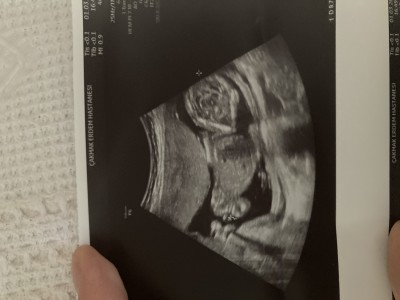

Sevgili anneler nub teoRisi bilenler yada cinsyst tahminlerine güvenenler yardımcı olabilr mi

Forografta 13 haftalık şuan 15 haftalık

Canım nub teorisi diye birşey var cinsiyeti %95 bilebiliyorlar

Canım erkke gibi nub a göre